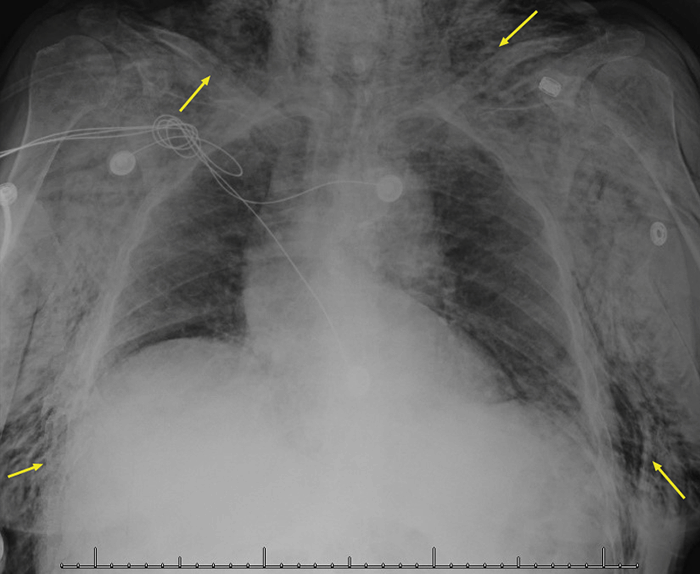

No significant pneumothorax was noted, but she had a large amount of subcutaneous emphysema (Figure 4). She also developed lateral herniation of the right lower lobe through the seventh and eighth rib space (Figure 5).

Figure 4. CXR Shows Extensive Subcutaneous Emphysema and Pneumoperitoneum. Published with Permission